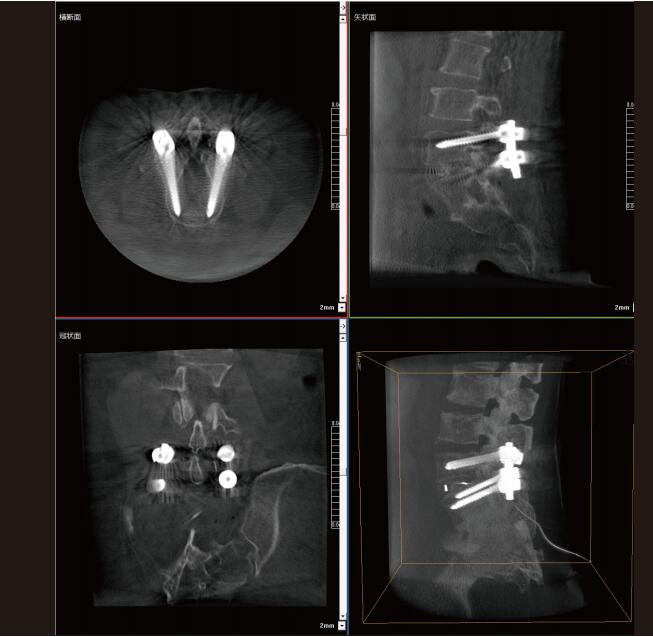

大功率平板三維C形臂PLX C7600術(shù)中實(shí)時(shí)生成:橫斷面、矢狀面、冠狀面及三維影像,可在任意切面、任意角度評(píng)估植入物和解剖結(jié)構(gòu)的相對(duì)位置,在手術(shù)室中即可完成結(jié)果的檢查確認(rèn),適用于全身各個(gè)部位。

2. 準(zhǔn)確評(píng)估,手術(shù)更安全。

大功率平板三維C形臂PLX C7600配置了30cm×30cm大尺寸動(dòng)態(tài)平板探測(cè)器,一次掃描可呈現(xiàn)更多組織信息,可以覆蓋: